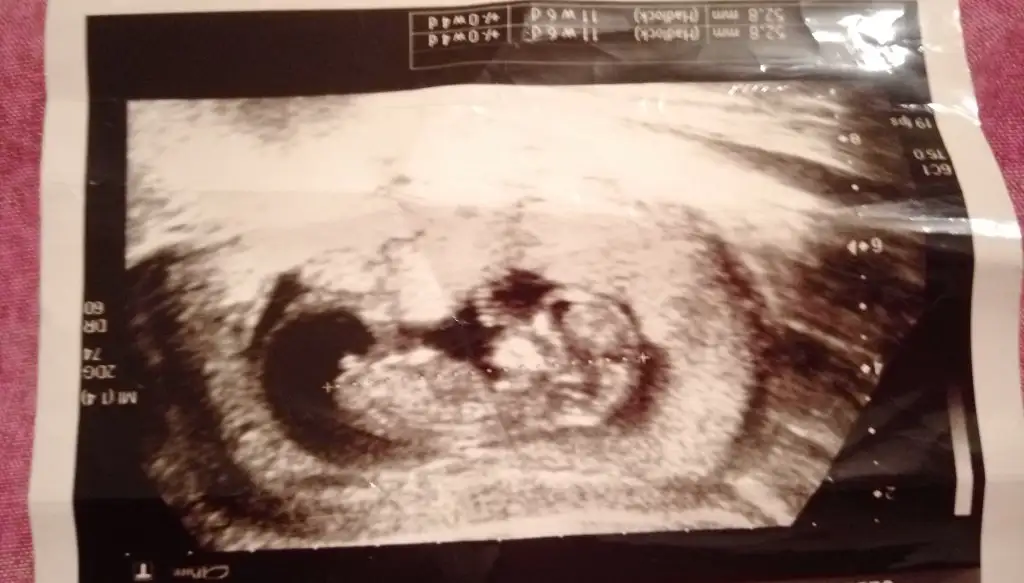

Erkek ve kız için 11 yada 12 hafta usg görüntüsü olmalı açıklamalar asagıda yazıyor 😊 rabbim herkesin gönlüne göre nasip etsin inşallah .. ecmain

[/B]Eki Görüntüle 473828 gordugunuz gibi ust taraftaki simgedende anlasildigi gibi eger cikinti paralel ise kiz

yok 30°lik bir aciyla yukari dogru bakiyorsa %99 oglunuz olacak demektir simdi bi kac ornek resimler daha koyacagim kiziminkide dahil

Eki Görüntüle 473829 bu bir erkek bebek genital nub cikintisi gayet yukarda

Eki Görüntüle 473831 simdi burada cikintilara bakin eger bel popo cizgisine paralel ise kiz

yok 30 derecelik bir aciyla yukari bakiyorsa erkek

yabancilarin hepsi biliyor bunu biz neden eksik kalalim gayet bilimsel simdi ellerinde11 12 13 ultrason fotografi olanlar alsin hemen baksin yada koyalim buraya yorumlayalim

Eki Görüntüle 473837 bu benim kizim cikinti gayet net ve ortada ve ben kizim diyooo